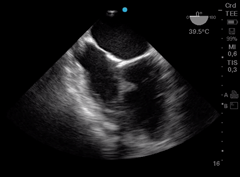

Otras veces la causa de PC perioperatorio es el tromboembolismo pulmonar. ETE tiene 80% de sensibilidad y 100% de especificidad para detectar embolia de pulmón. (Figura j)

Figura j: Imagen medioesofágica tracto de entrada y salida de VD.Trombo que migra del ventrículo derecho hacia la arteria pulmonar.